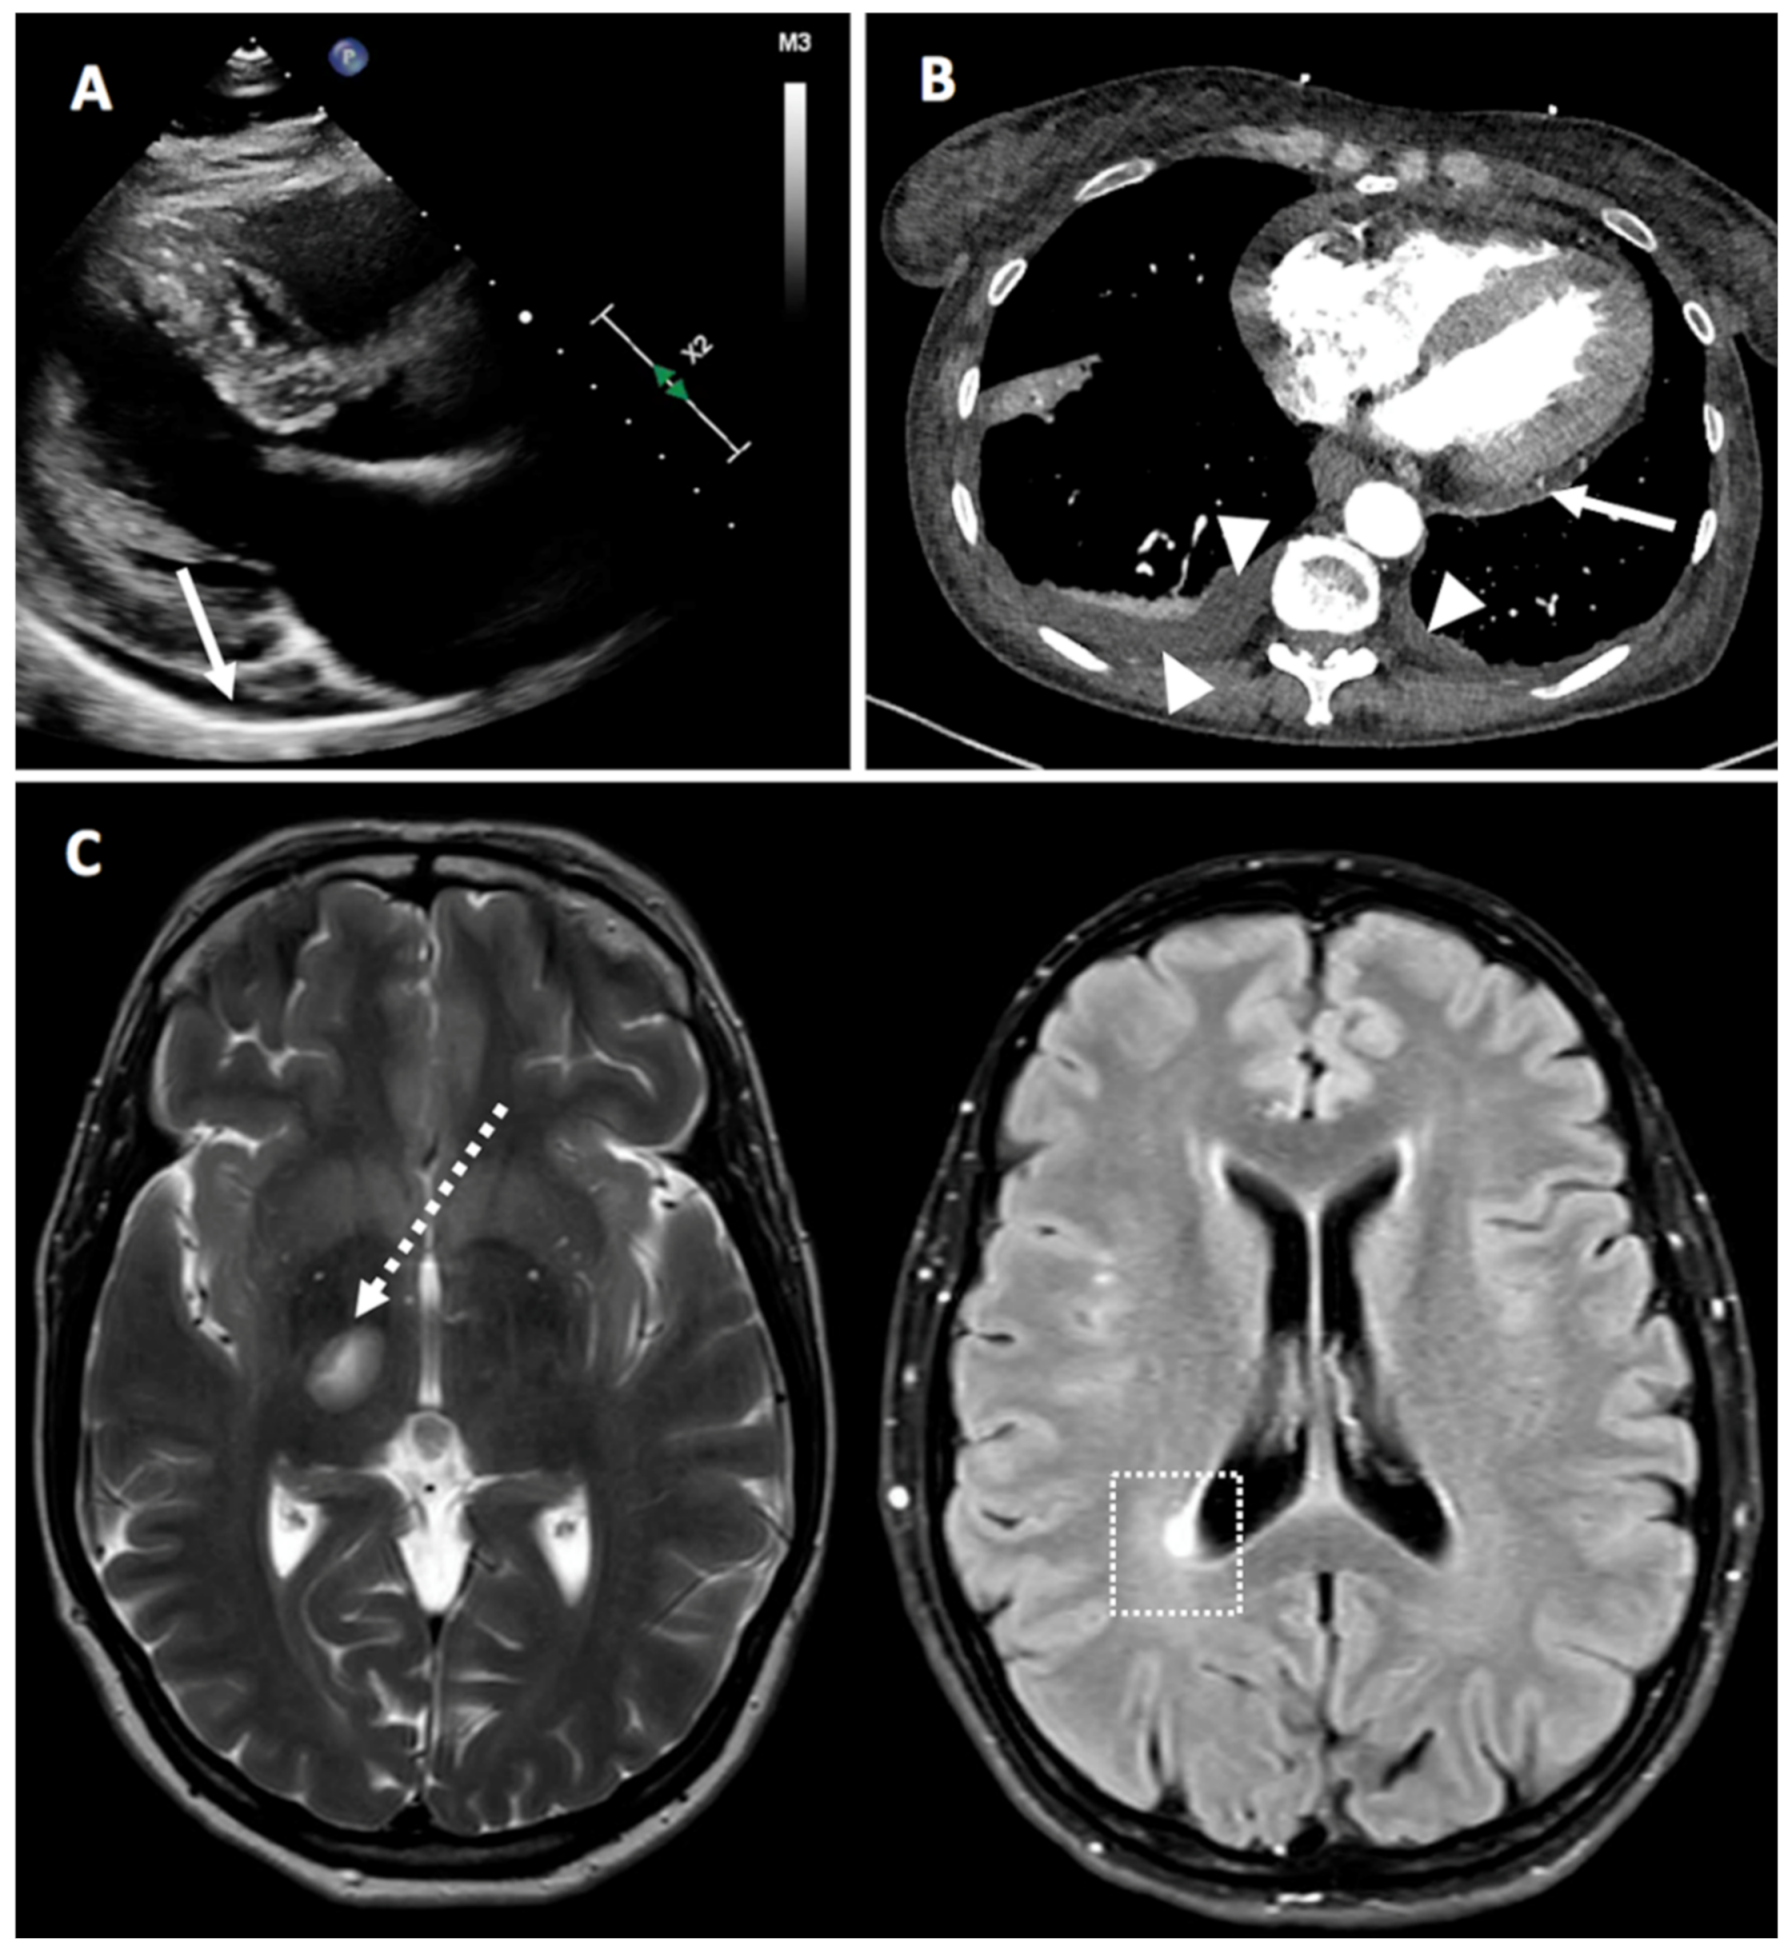

Figure 4.

Panel (A) (Case 4)—Parasternal, long axis view from a 2-D echocardiogram showing a small-sized posterior pericardial effusion (white arrow). Panel (B) (Case 27)—Computerized tomography scan demonstrating posterior pericardial effusion (white arrow) and bilateral pleural effusion (white arrowheads). Panel (C) (Case 7)—Magnetic resonance imaging of the brain showing demyelinating lesions in the left mesencephalic (dotted white arrow) and in the right peri-ventricular occipital white matter (white dotted square).

We observed two cases of pericarditis that we considered to be more autoinflammatory than autoimmune (Figure 4, in particular Figure 4A,B). Notably, one case was particularly suggestive of vaccine-induced inflammation as with each vaccination, pericarditis occurred 4 days after the first dose and a flare 4 days after the second dose. Both episodes were treated with nonsteroidal anti-inflammatory drugs (NSAIDs) and colchicine and responded well.